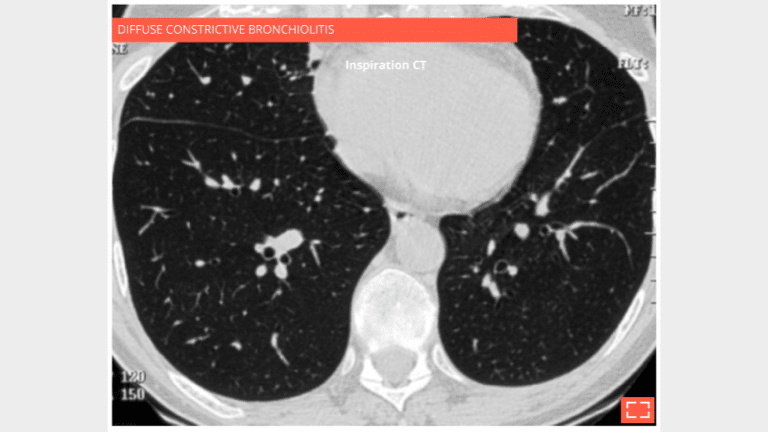

Bronchiolar mosaic attenuation

Diffuse constrictive bronchiolitis in a bone marrow transplant patient with shortness of breath and obstructive disease.

Inspiratory CT: the lung is over inflated, hypodense overall, but homogeneous.